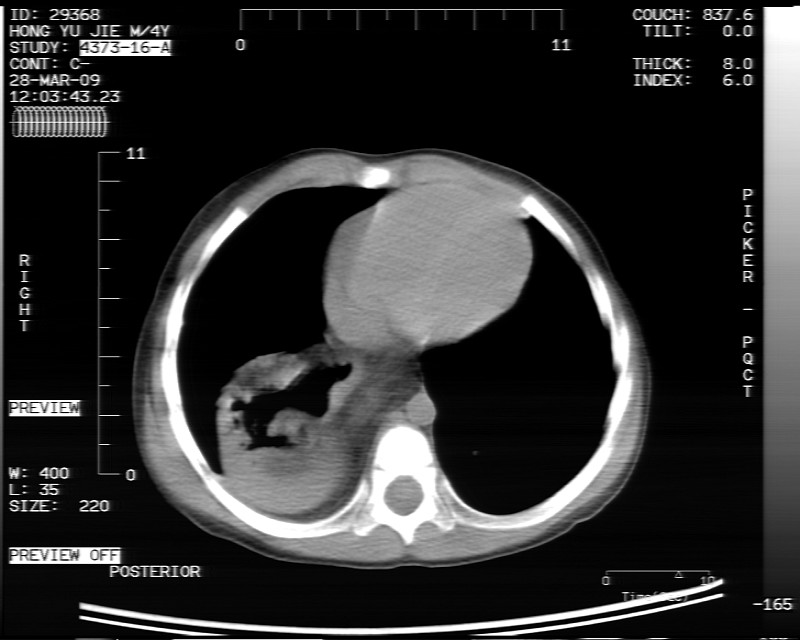

标题: PED1814:胸片体检发现右下肺病变。

男性,3岁,斜疝术前常规检查胸片体检发现右下肺病变。咳嗽,无发烧。

内有气体,液平面,考虑食管裂孔疝可能性大。建议食道钡透。

有液气平面,前部肺纹理聚集(受压改变),周围肺野及相邻胸膜清晰,支持膈疝,可吞服造影剂看一下。

考虑膈疝(右侧胸腹膜裂孔疝?)。